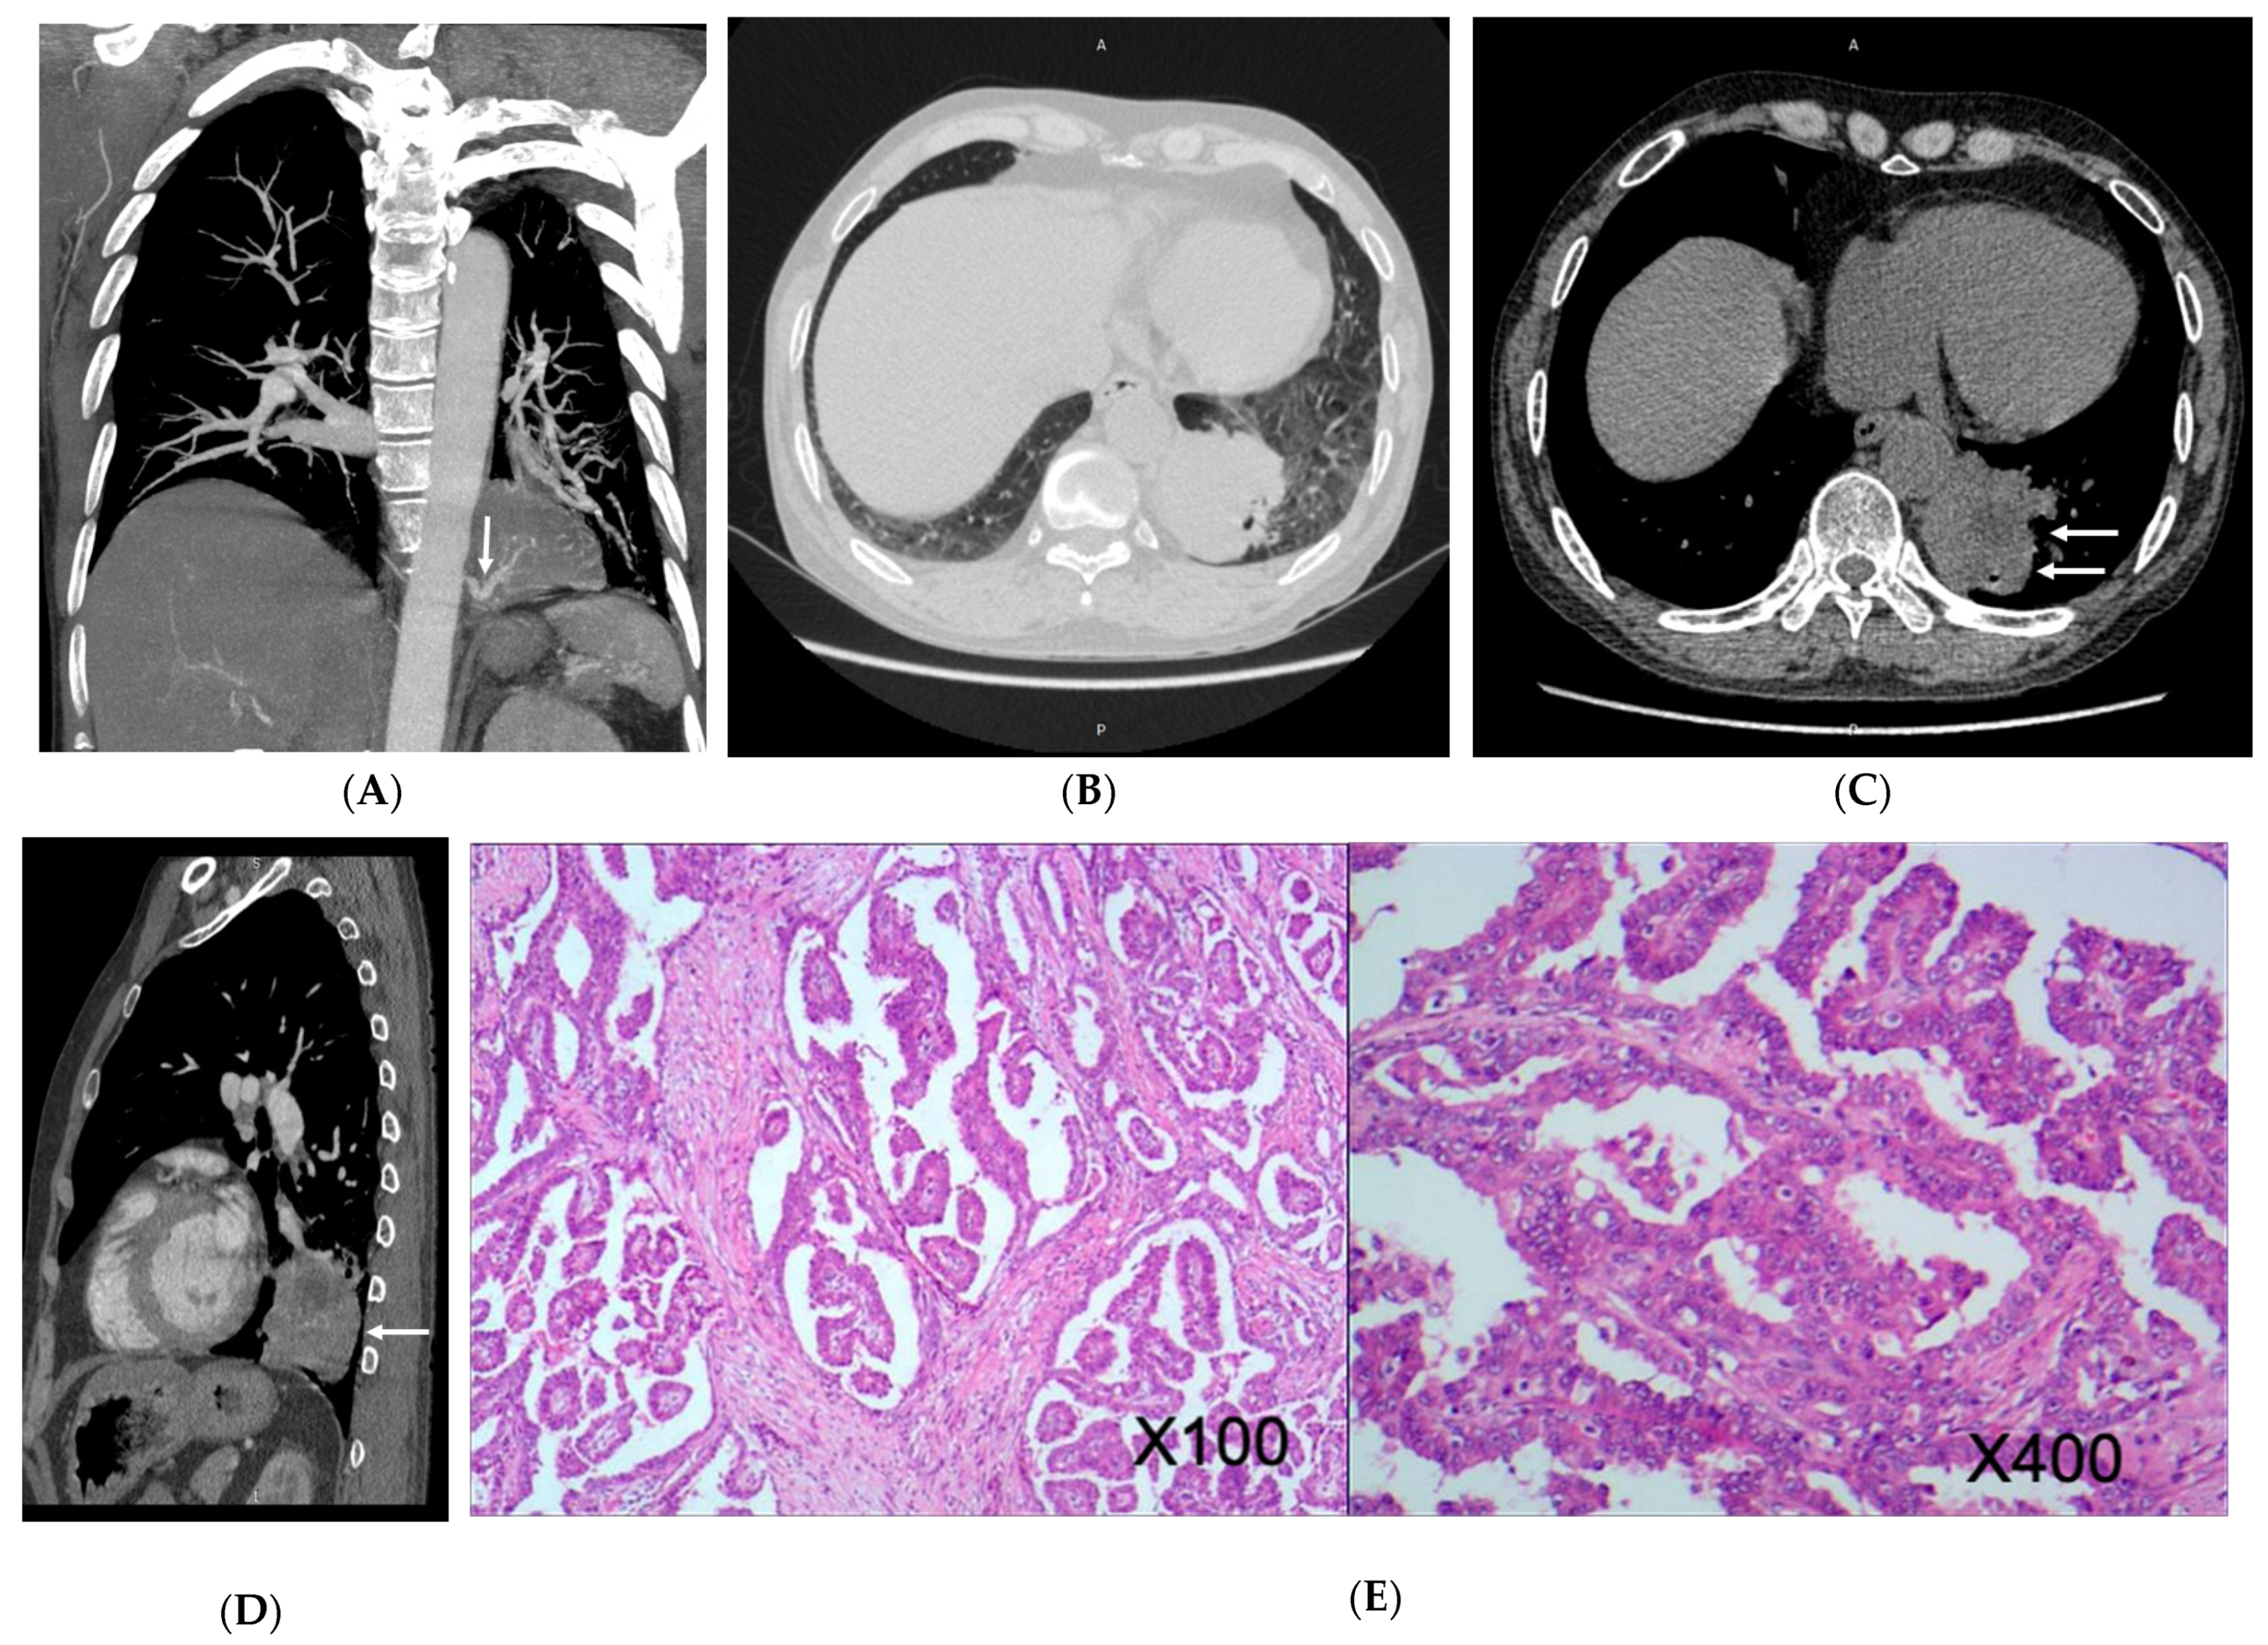

3.2. Imaging Appearances of CTPA